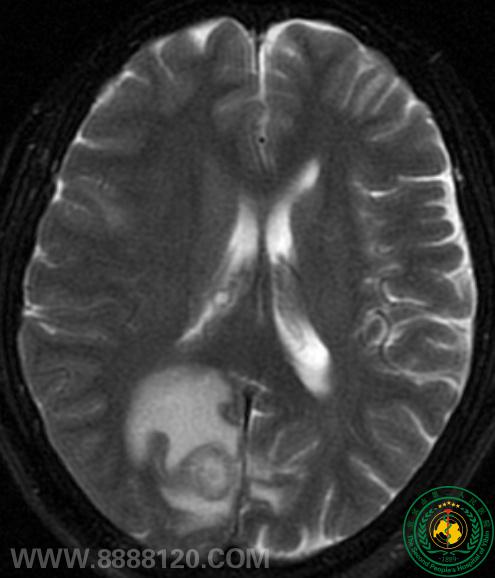

PET/CT发现一转移癌患者的隐匿性原发性肿瘤

PET/CT发现一转移癌患者的隐匿性原发性肿瘤7429